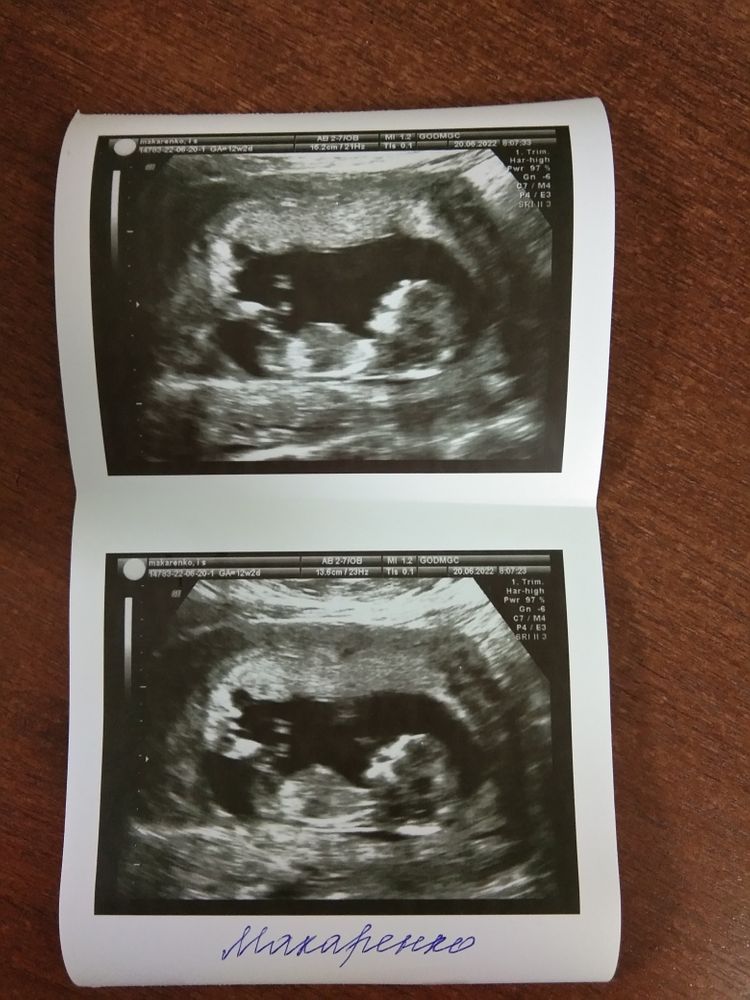

1 Скрининг. Неужели девчуля?

У меня сегодня тоже первый скрининг будет!)))) очень переживаю. А как по фото можно понять, что девочка? Там все так нечетко 🙂

Ирина , мне рассказали про градус полового бугорка) типо если почти параллельно спинке - это девочка) у мальчиков выше половой бугорок) безусловно нам, кто не шарит только догадываться) особенно по фото) УЗИсты, они конечно смотреть в движении и глаз алмаз) Есть те, кто если не особо видит сам - ничего и не скажут))) У меня вот УЗИстка сама предложила озвучить кого она видит уже минут через 5))) я даже и не думала))) говорю: а давайте)))на втором скрининге попрошу уже тогда написать на бумажке и сразу с мужем закажем хлопушку)))) иначе долго терпеть не смогу))) хахах

у меня недавно был очень похожий пост))) тоже фото 1 скрининга, где предположили дочку))) и почти 95% читательниц бейби блога прокомментировали что дочка))) есть что-то схожее с Вашим фото))

Вроде как девочка😊